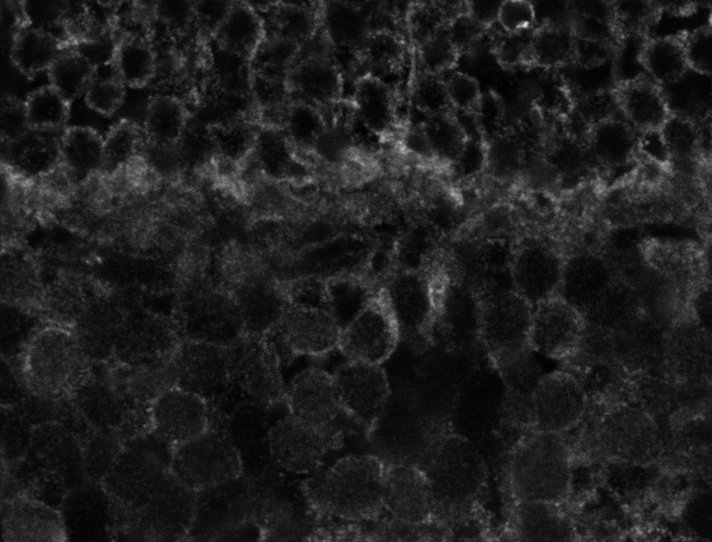

Nuclei

Nuclei - Bis

Nuclei - Bip

Nuclei - Bipolar